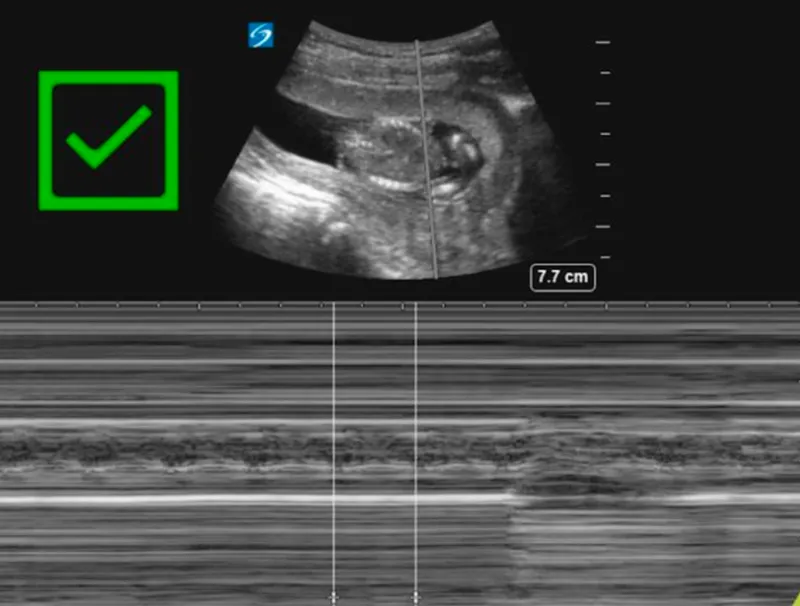

- Bedside Ultrasound:

- Check for fetal cardiac activity, placental location (r/o previa), and amniotic fluid volume.

- Not sensitive for abruption initially.

- Cardiotocography (CTG): Continuous monitoring for ≥4-6 hours for all viable pregnancies post-trauma.

- Monitors for contractions & fetal distress (e.g., decelerations).